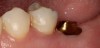

Plugging into digital workflows provides opportunities to integrate CAD/CAM technologies at every step of the treatment process for dental implants. In another example, a patient presented with a failing tooth No. 8 (Figure 6 and Figure 7). After discussing treatment options, the patient chose to forgo any treatment to address tooth and soft-tissue asymmetries and wanted to proceed with a dental implant-supported restoration without additional treatment. After integrated 3-dimensional planning, the tooth was extracted, and then an implant and the final custom CAD/CAM abutment (titanium base with zirconia supra-structure) were placed with a provisional restoration in the same visit (Figure 8 and Figure 9). Soft-tissue grafting was also done at the same visit to address the deficient buccal tissue height on No. 8 (Figure 10). At 3 months, the patient presented for the final restoration, with excellent healing around the implant (Figure 11) and soft-tissue healing guided by the custom abutment (Figure 12).

Fig 6. Clinical presentation of patient with a failing tooth No. 8.

Fig 7. Preoperative radiograph showing previous endodontic therapy on tooth No. 8.